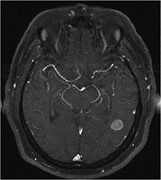

BRAF V600D mutation in a paediatric high-grade glioma

Aisling Ní Nualláin and others

Journal of Surgical Case Reports, Volume 2016, Issue 10, October 2016, rjw150, https://doi.org/10.1093/jscr/rjw150

Cerebral metastases from Merkel cell carcinoma: long-term survival

S. Honeybul

Journal of Surgical Case Reports, Volume 2016, Issue 10, October 2016, rjw165, https://doi.org/10.1093/jscr/rjw165